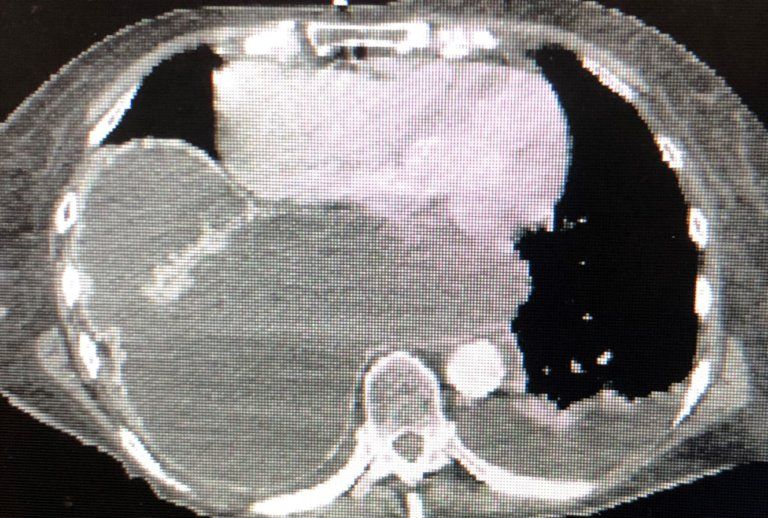

Endocrine Case Report Coffee Ground Emesis

From www.hcplive.com